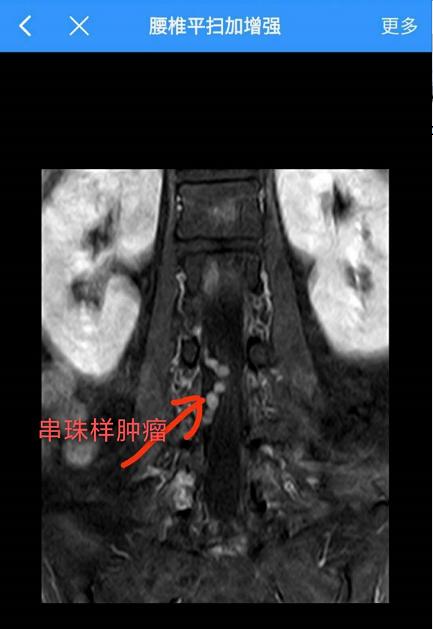

腰椎间盘突出十几年,没想到是椎管里长了“串珠”样的瘤子

“以前一直以为只是腰椎间盘突出,吃了很长一段时间的药,没见好。后来到人民医院骨科看看,做了腰椎磁共振检查,医生说好像脊椎(椎管)里面长了瘤子。”潘阿姨如是说。

“腰椎间盘突出症是临床导致腰部及下肢疼痛最常见的原因,虽然腰椎间盘突出症比较多见,但也不可忽视其他疾病的可能,其中椎管肿瘤就需要特别注意。”冯玛静解释道,“椎管肿瘤如果不手术,以后很可能造成功能障碍,甚至肢体残疾。椎管瘤不少见,但是像这种‘串珠样’的瘤子,连浙二的专家也说,只见过四例。瘤子长在L4运动神经根上,把这一串肿瘤从同一根神经上完整切除,同时还要保障神经功能完好,手术难度和风险都极高,能顺利开展这样的高难度手术并让患者在‘家门口’受益,我感到非常幸福!”